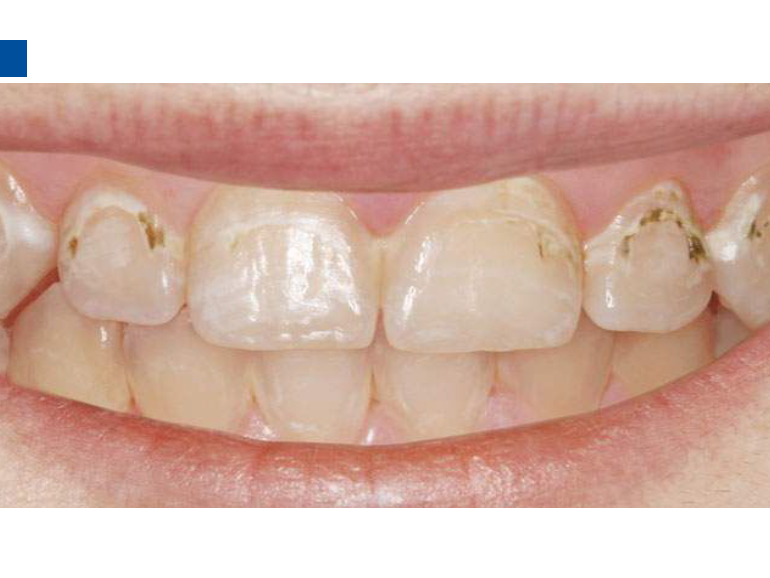

二、爱康渗透树脂唇颊面装Icon Caries Infiltrant – vestibular,治疗唇颊面釉质早期龋。(整个套装包含一次治疗两至三个早期龋损所需的材料。一次性使用,如果邻牙有类似病变可一并治疗)。

3、小心旋转注射器柄部,将足量材料涂布于龋损区域之上,等待2分钟,并用棉球去除多余材料,酸蚀范围应至龋损外2mm处,如果正畸患者托槽取下后发现牙面大范围早期龋损则需酸蚀整个牙面。(单手可完成注射器操作)。

lcon渗透基于封闭釉质龋空隙的一种特殊树脂的渗透,封闭釉质龋小孔,从而阻断致龋酸传播途径,阻止龋病进一步发展。这种材料操作方法简单,对牙体组织损伤轻微,不用通过麻醉和磨切牙体来达到加固脱矿釉质,同时可以改变釉质龋表面的白色或棕色改变,达到美观修复效果,是对龋病微创治疗的突破。